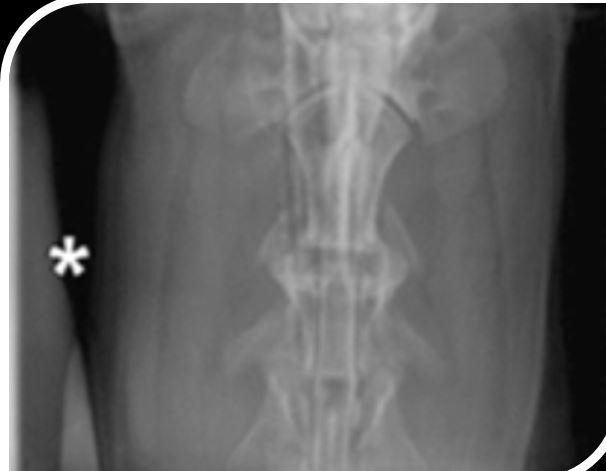

5

Q

Artifact? Fix?

A

Rebound or uberschwinger

Minimize edge enhancement